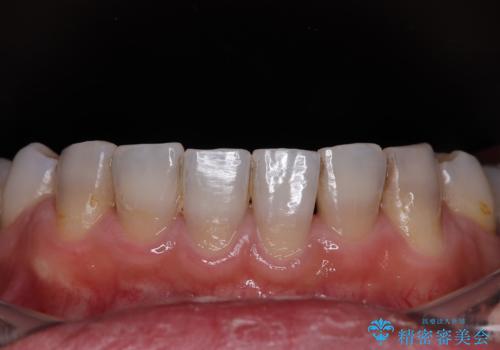

薬剤の影響で変色した歯を自然に オールセラミッククラウンによる審美歯科治療

- 口元の突出感を改善するための抜歯矯正を終えた患者様ですが、幼少期からの変色した歯をセラミッククラウンにて自然な色合いに変えていくこととしました。

口を開けたときに目につく範囲を希望されたため上下ともに8本ずつをオールセラミッククラウンによる補綴治療を行うこととしました。

近年では大変珍しいですが、胎児あるいは乳幼児期の抗生物質の影響で永久歯が変色してしまうことがあります。

ホワイトニングでの改善は期待できないため、オールセラミッククラウンによる補綴治療が必要となります。